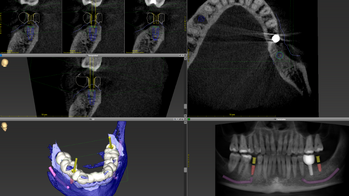

Zahnärztliche Implantate

Ein weiterer Fokus unserer Klinik für Mund-, Kiefer- und Gesichtschirurgie am UKS liegt auf der dentalen Implantologie für komplexe Fälle und vorerkrankte Patientinnen und Patienten. Zahnimplantate werden zur Verankerung von Kronen, Brücken oder Prothesen im Kiefer eingesetzt und zielen auf die Wiederherstellung der Kaufähigkeit ab. Eine präzise Planung der Operation ist entscheidend, um Implantate optimal zu positionieren und angrenzende Risikostrukturen zu schützen. Dabei nutzen wir häufig digitale Planungsprogramme, die durch spezielle Schablonen die Präzision und Sicherheit während der Operation verbessern. Zahnimplantate sind in der Regel keine Leistung der gesetzlichen Krankenkassen, außer bei Patienten mit Tumorerkrankungen oder angeborenen Fehlbildungen. Wir beraten Sie gerne zu individuellen Lösungen für Ihre dentale Rehabilitation, auch in Kooperation mit Ihrer Hauszahnärztin oder Ihrem Hauszahnarzt.